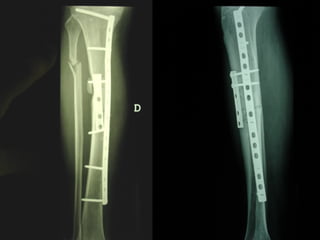

Dal Gennaio 2000 al Febbraio 2006 abbiamo trattato 167 fratture chiuse  con placca percutanea  in 164 pazienti :  27 lesioni diafisarie di gamba, 12 piloni tibiali ,  11 fratture prossimali di tibia, 36 fratture sovracondiloidee di femore, 17 fratture diafisarie di femore, 43 fratture metaepifisarie prossimali di omero, 21 diafisarie d’omero.  156 guarigioni 8 fallimenti

Dal Giugno 2002 al Dicembre 2004 abbiamo trattato 5 fratture esposte: 3 di tibia e 2 di ulna 5 guarigioni

I buoni risultati ottenuti dipendono da 5 punti fondamentali:   una accurata riduzione percutanea della frattura  precise vie di accesso  l’utilizzo della placca che consenta il più lungo braccio di leva possibile il pretensionamento della placca  una sintesi con un ridotto numero di viti